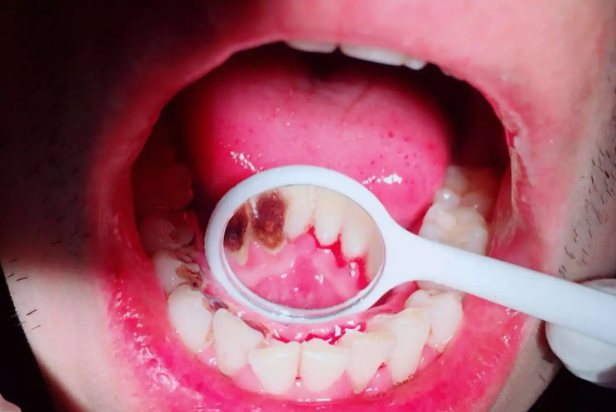

1.牙周脓肿

牙齿在根尖感染时会形成急性根尖脓肿,根尖脓肿破溃后就形成慢性根尖周炎,牙周脓肿主要表现的症状是牙龈出现肿胀、隆起,其是靠近龈缘的部位,有较明显的脓肿区域。并且在牙周隆起的部位,会感觉到明显的波动。会形成脓性的液体从肿胀区流出。牙周脓肿疼痛会比较明显。